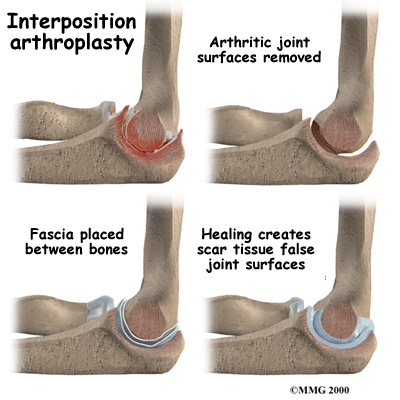

Before the invention of high-quality artificial joints, surgeons used many techniques to keep the bone surfaces of arthritic joints from rubbing against each other. One of these techniques is distraction interposition arthroplasty. This procedure involves placing a piece of tendon or fascia between the bony surfaces of the elbow joint. Fascia is a connective tissue, similar to tendon that lies in a flat sheet. It covers the muscles and acts as a divider between different compartments of the body.

Before the invention of high-quality artificial joints, surgeons used many techniques to keep the bone surfaces of arthritic joints from rubbing against each other. One of these techniques is distraction interposition arthroplasty. This procedure involves placing a piece of tendon or fascia between the bony surfaces of the elbow joint. Fascia is a connective tissue, similar to tendon that lies in a flat sheet. It covers the muscles and acts as a divider between different compartments of the body.

As the joint heals, the tendon or fascia forms a cushion of thick, tough tissue between the bones. The tissue pads the ends of the bones and reduces pain while still allowing the elbow to move.

Interposition arthroplasty is rarely indicated but may be used in rare cases. This procedure works fairly well in the elbow but doesn't work very well in the weight-bearing joints of the hip, knee, and ankle.